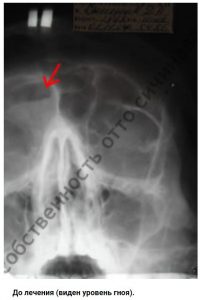

Если человек болен синуситом, то это значит, что у него разросшаяся слизистая, которая приводит к закрытию соустья и, непосредственно, к поступлению в них воздуха. Пациенту начинает труднее дышать, в слизистой не циркулирует воздух, что приводит к ее пересушке и образованию полипов. Еще одной проблемой является слизь, которая скапливается в больших количествах и представляет собой настоящий рай для бактерий.